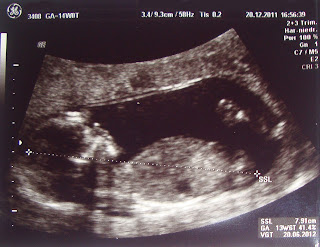

Hier seht Ihr das Ergebnis des weltbesten Produkttests!

Und da mir seitdem 24 Stunden am Tag übel war und ich genauso lange schlafen könnte, habe ich mir erstmal eine kleine Blog-Pause verordnet. Jetzt bin ich in der 14. SSW und nun geht es mir wieder besser. Gestern hatte ich meine 3. VU beim FA. Alles super!

Der Arzt fragte mich dann, ob ich denn das Geschlecht wissen möchte. Da ich ein sehr neugieriger Mensch bin, wollte ich das natürlich sehr gerne wissen.

Und … es wird ein ? Man konnte nichts erkennen. Einerseits zwar schade, aber andererseits kann ich mir nun noch einen weiteren Monat ausmalen, was es werden könnte. Auch schön 😉